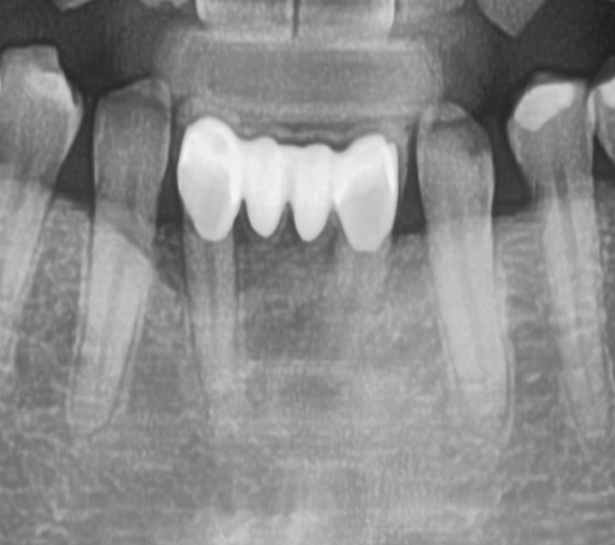

마지막으로 Short Abutment를 사용하여 zirconia cement retained type 최종 보철물을 완성하였다 [그림 11, 12].

최종 보철물 제작 2개월 후 구강 내 사진에서 만족스러운 연조직 치유 양상을 확인할 수 있다 [그림 13].